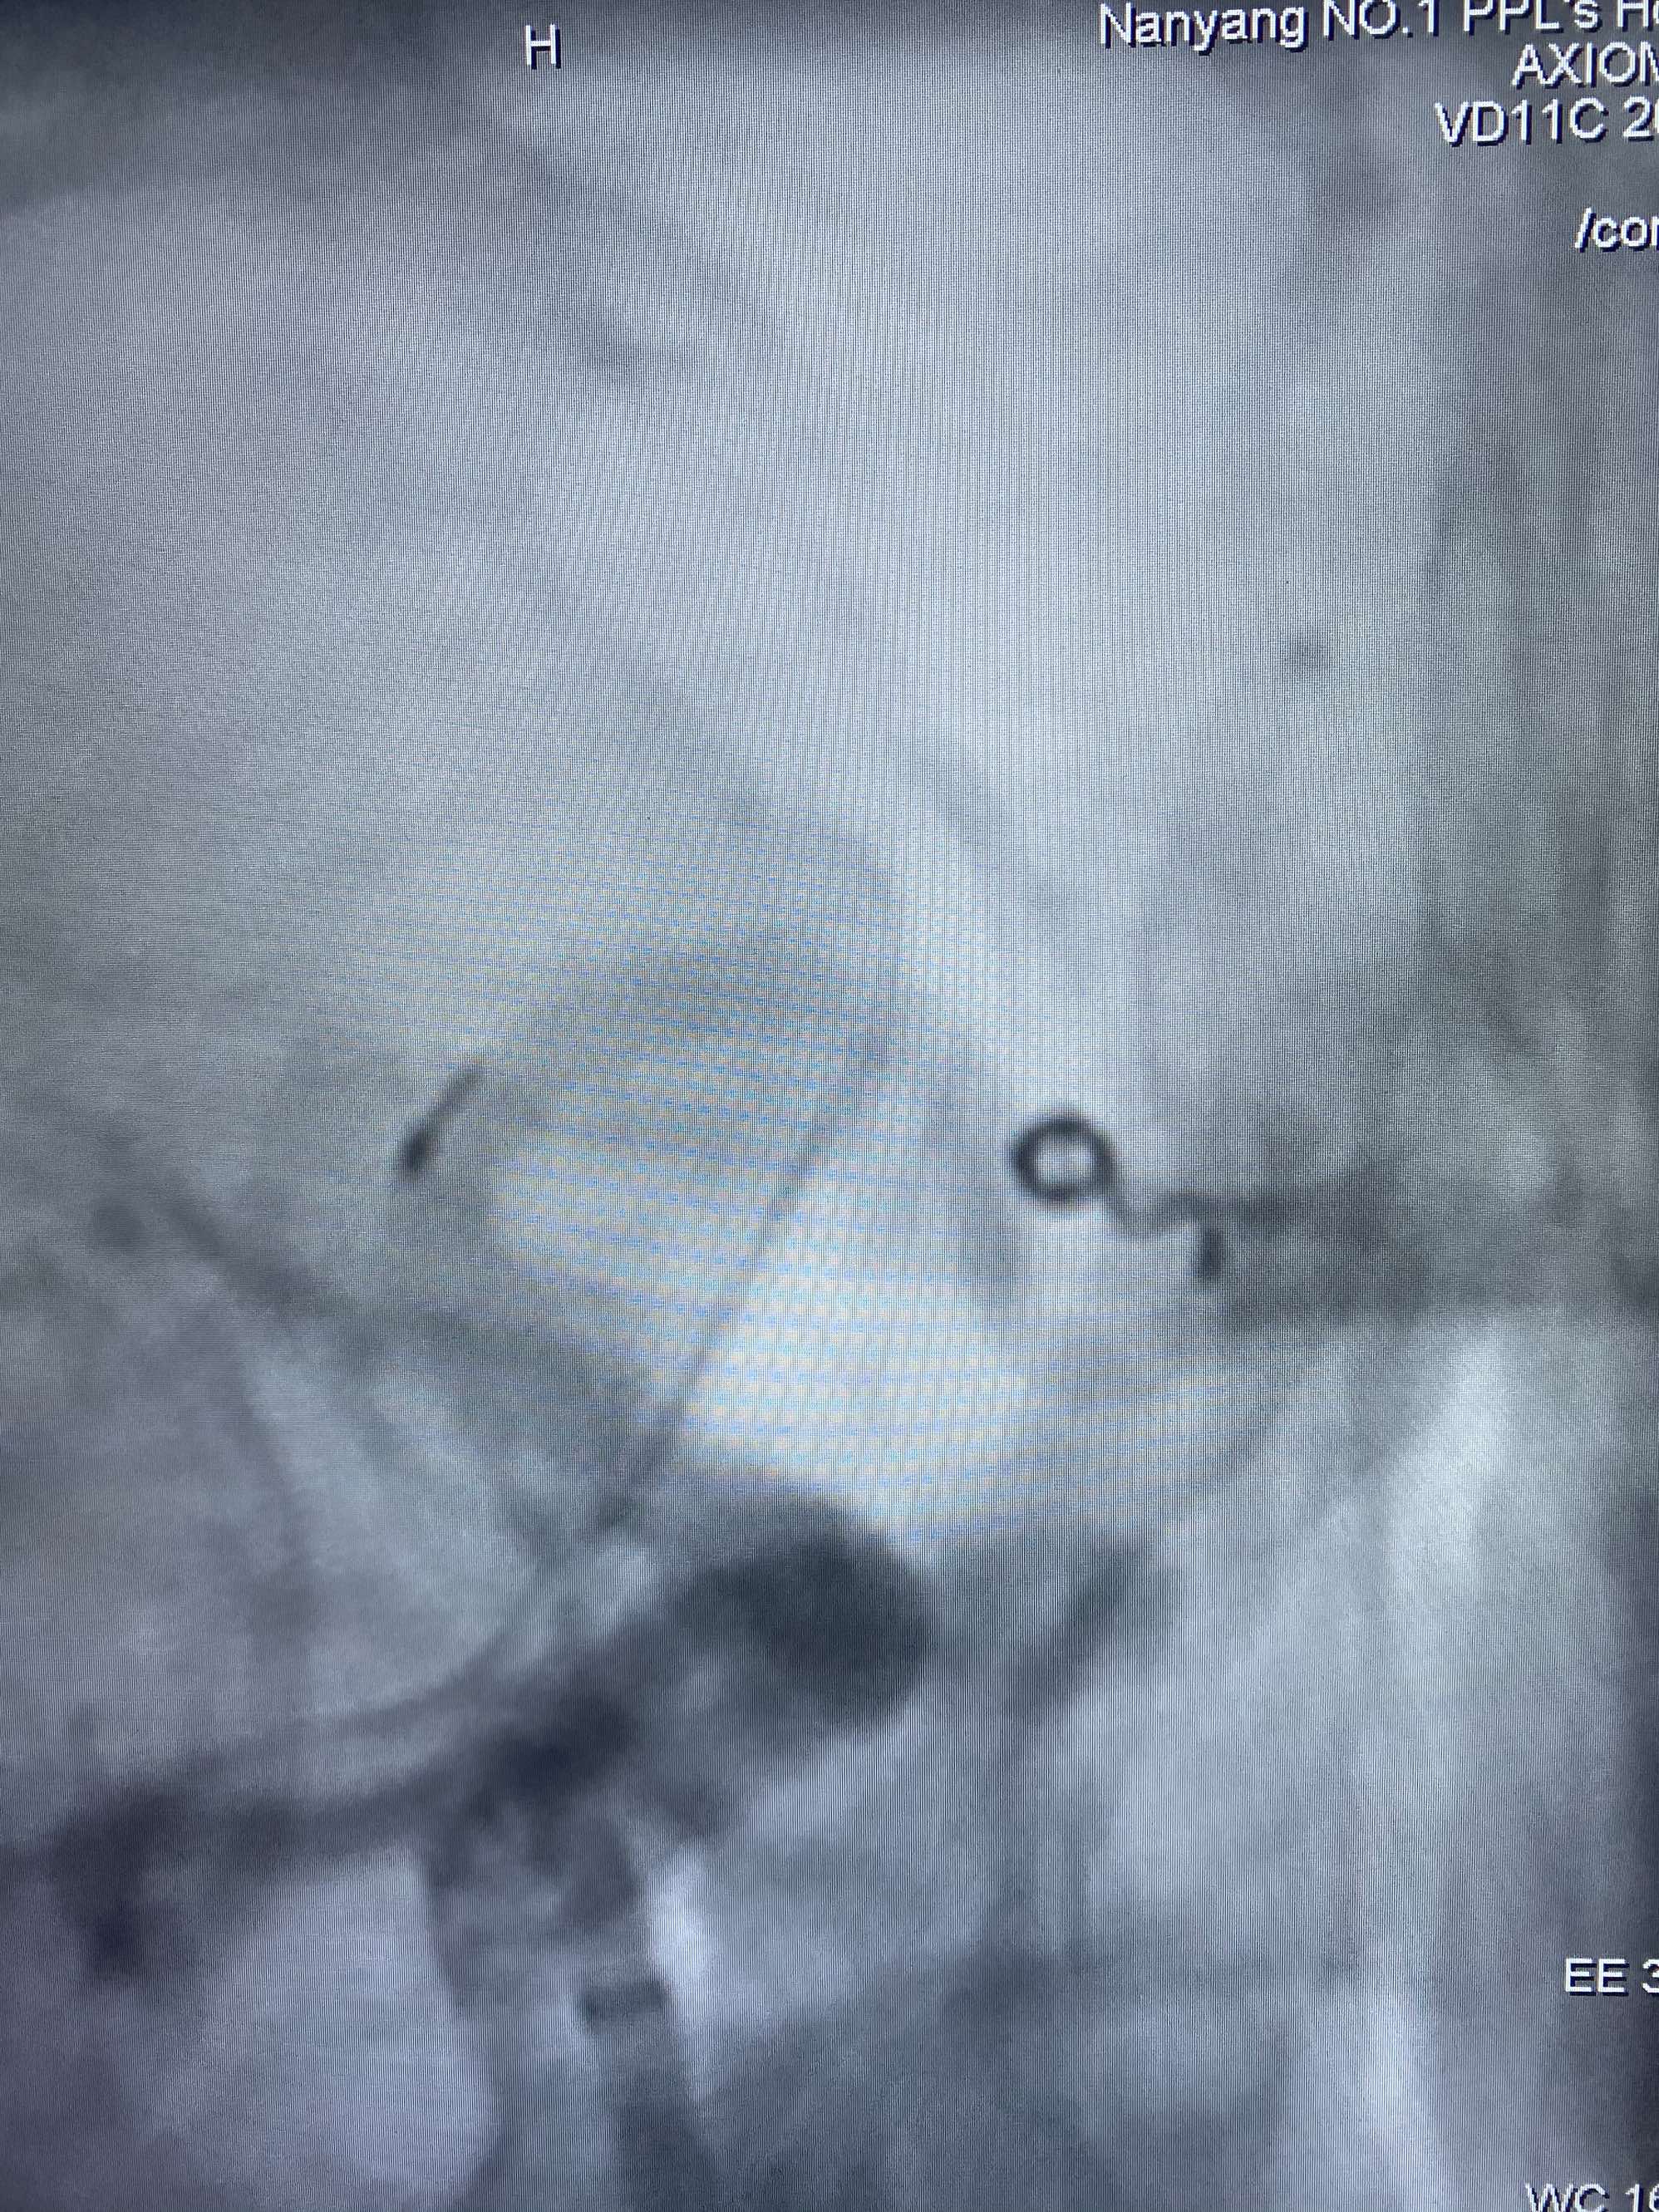

MLS,M79Y,sah,双侧MCA烟雾病,Heubner返动脉瘤,前交通段开窗,细支发出Heubner返动脉,瘤颈细长,瘤颈口比微导管细,弹簧圈2mmx3cm“隔山打牛”填塞治愈,Heubner返动脉保留。